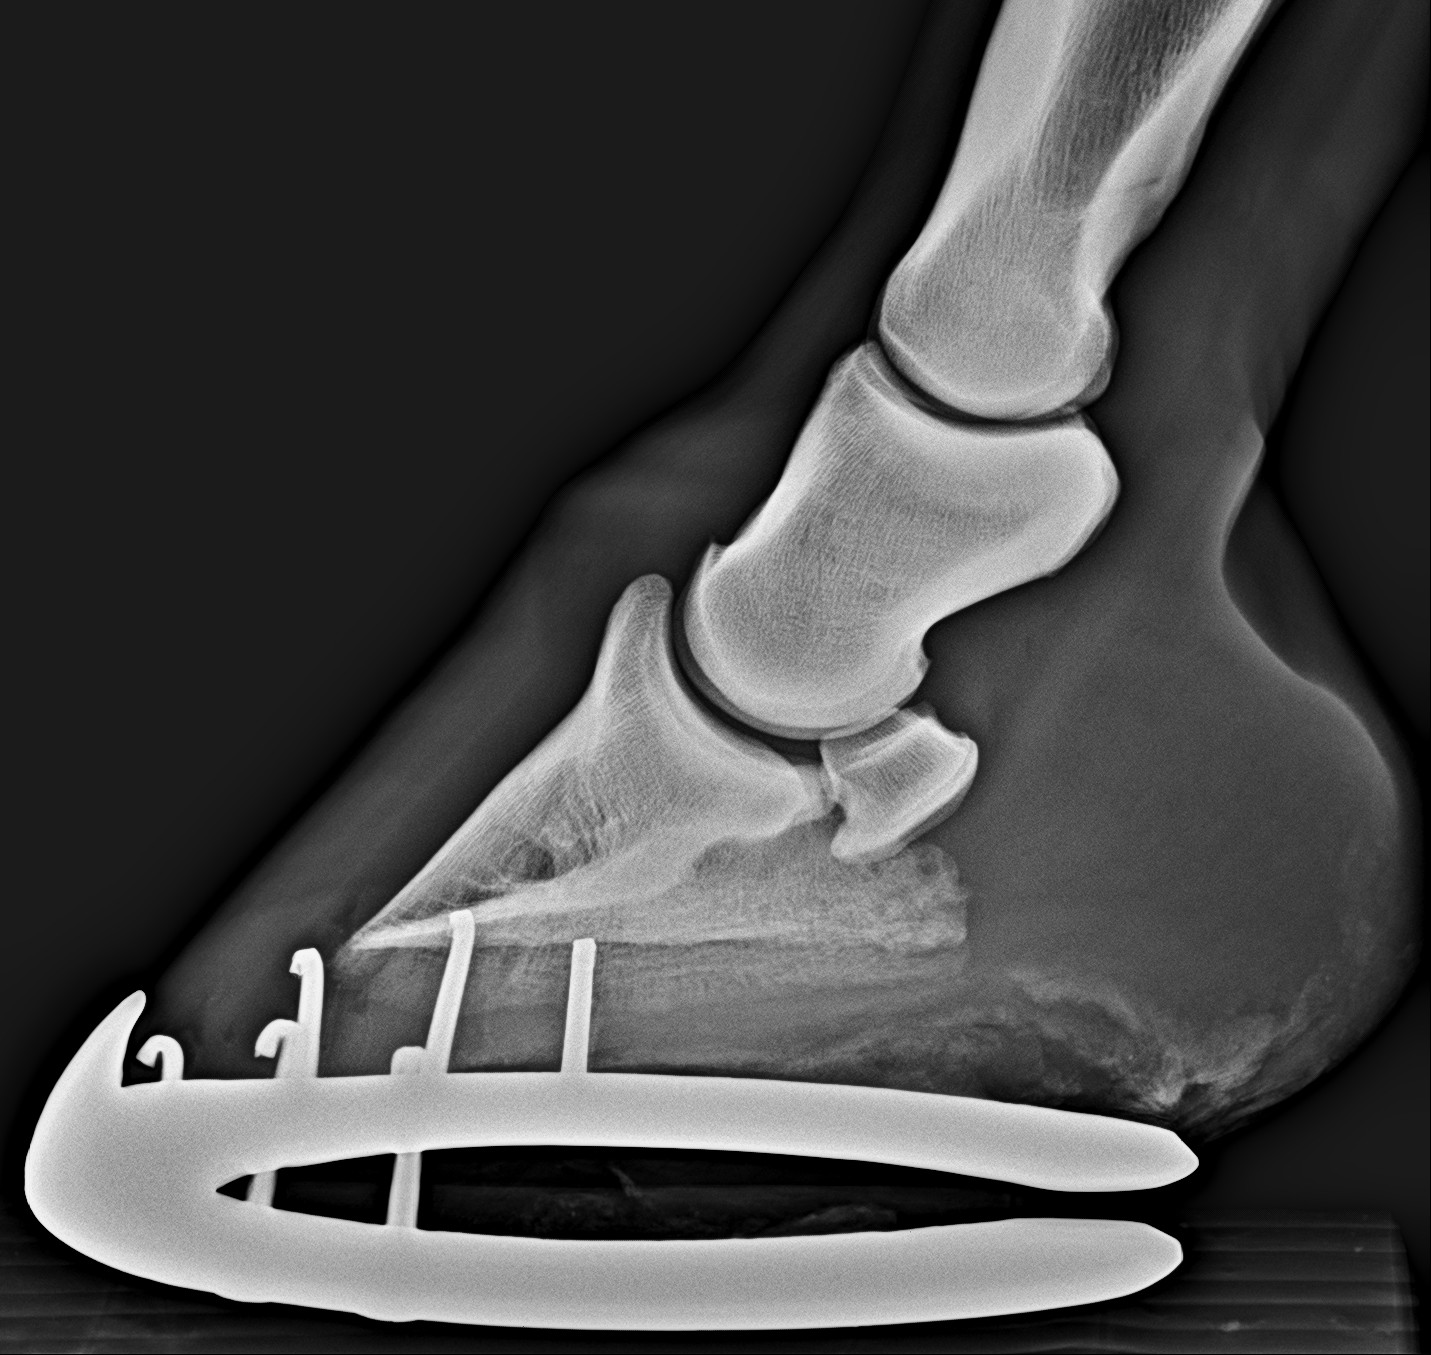

Így néz ki egy egészséges pataízület